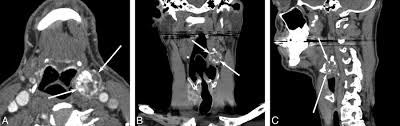

According to an article in the official journal for the American Academy of Otolaryngology hyoid bone fractures usually cause symptoms such as difficulty swallowing and pain upon head rotation. All patients presented with throat pain and had tenderness of 1 63 or both 38 greater cornua of the hyoid bone. The pain starts below the angle of the mandible and radiates into the anterolateral neck.

33 The connections to the hyoid bone explain the radiating symptoms. The pain starts below the angle of the mandible and radiates into the anterolateral neck. Hyoid Bone Syndrome ES can have many symptoms in common. The most common symptom is point tenderness at the lateral aspect of the hyoid or superior cornu of the thyroid cartilage. A further syndrome relating to the hyoid bone the styl-ohyoid syndrome was reported by Shenoi 1972 with a specific finding of tenderness over the lesser cornu of the hyoid bone but very similar symptoms. Its those darn cranial nerves that get irritated make us hurt sometimes feel. Other symptoms of Eagle syndrome include. Hyoid bone syndrome is a type of cervicofacial pain that is caused by degeneration of the greater cornu of the hyoid at the attachment of the stylohyoid ligament. When it flares up even without pressing it often feels like someone has shoved forceps through my skin into the soft area behind my chin upwards toward my mouth and is pinching them closed around the skin and muscle etc between the points.

Nonspecific cervical pain is a common complaint in primary ear nose and throat clinic patients. Ringing in your ears. It is often missed and yet is readily treatable. Symptoms of hyoid bone dislocations include. The most common symptom is point tenderness at the lateral aspect of the hyoid or superior cornu of the thyroid cartilage. Hyoid Bone Syndrome ES can have many symptoms in common. Treatment by an injection of a mixture of depomedrone and one per cent lignocaine is very effective.